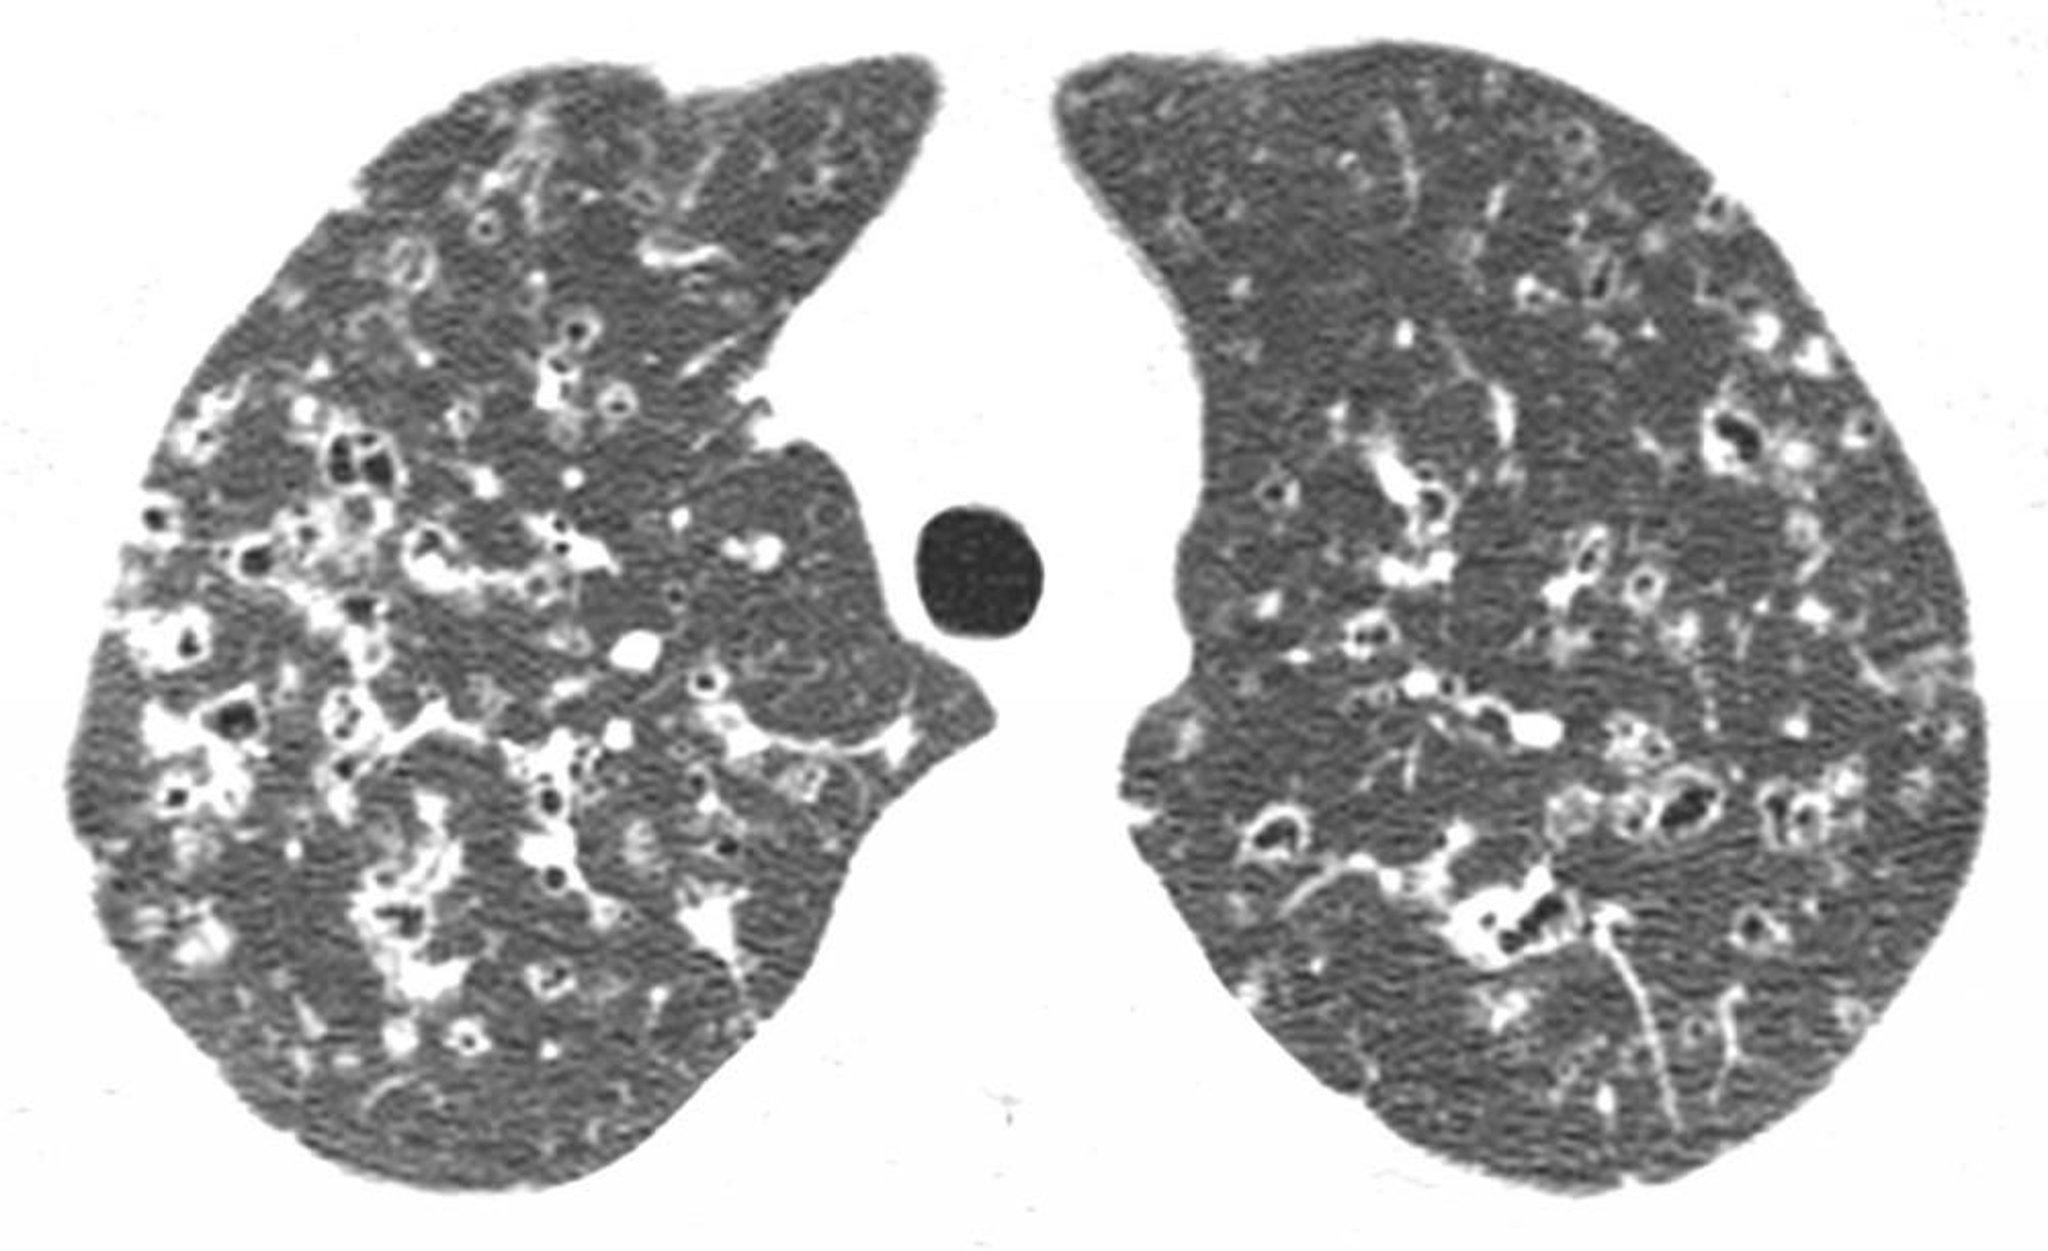

High-resolution CT through the upper lobes shows nodules and irregular air-density cysts, usually in the upper and mid-lung regions. These findings are characteristic of Langerhans cell histiocytosis in a patient with a history of smoking.

Image courtesy of Harold R. Collard, MD.